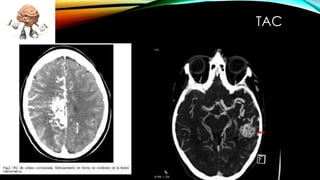

Este documento describe las malformaciones arteriovenosas, una patología vascular congénita poco común que ocurre en menos del 1% de la población. Se caracteriza por una masa retorcida y de color grisáceo que se atribuye al desarrollo anómalo del sistema venoso cerebral. Puede causar una variedad de síntomas como dolores de cabeza, convulsiones, debilitamiento muscular y problemas de visión u oído. Su diagnóstico requiere exámenes de angiografía, tomografía computarizada o resonancia magnética